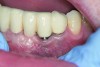

Following active therapy, probing depths of 4 mm or less (Figure 1 and Figure 2) and the absence of bleeding on probing contribute to improved health and stability. Increasing probing depths should alert the therapist to identify etiology and determine whether active periodontal therapy is warranted. The absence of bleeding on probing is a strong predictor of stability, and although the presence of bleeding does not always result in attachment loss, it remains an important parameter to evaluate.14 Bleeding on probing is also an important parameter for assessing implant health during maintenance. Serino et al15 evaluated 27 patients with 19 dental implants over 5 years. Patients were seen every 6 months and they concluded that bleeding on probing was a good predictor for attachment loss and disease progression around the implants (Figure 3).

Fig 1. A deep pocket of 7 mm prior to active periodontal therapy.

Figure 1

Fig 2. Following periodontal regenerative therapy, the tooth with a 3-mm probing depth, which facilitates maintenance.

Figure 2